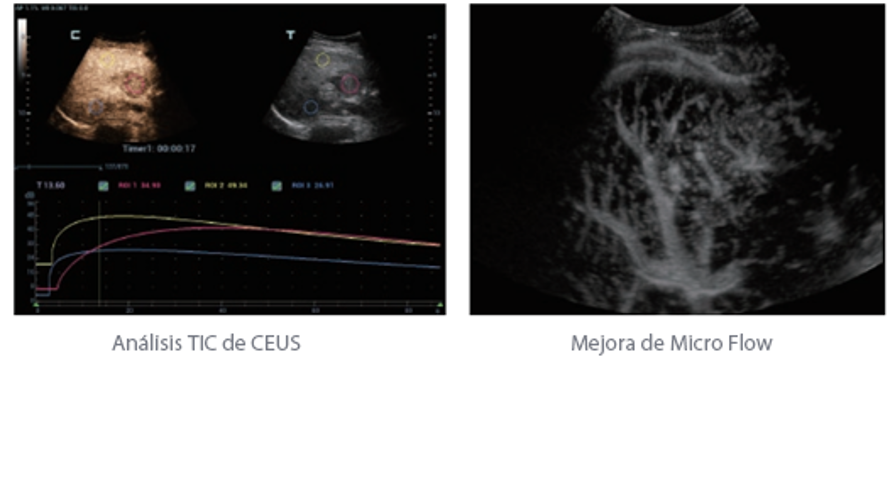

Además de la calidad de imagen de primer nivel, Resona?7 también mejora las capacidades de investigación clínica con el revolucionario V?Flow para la evaluación hemodinámica vascular y con la adquisición de planos más inteligente a partir de conjuntos de datos 3D para el diagnóstico del SNC fetal. Al combinar el funcionamiento multitáctil basado en gestos más intuitivo y todas las características clínicas esenciales, Resona?7 realmente lidera las novedades en innovación de ecografías.